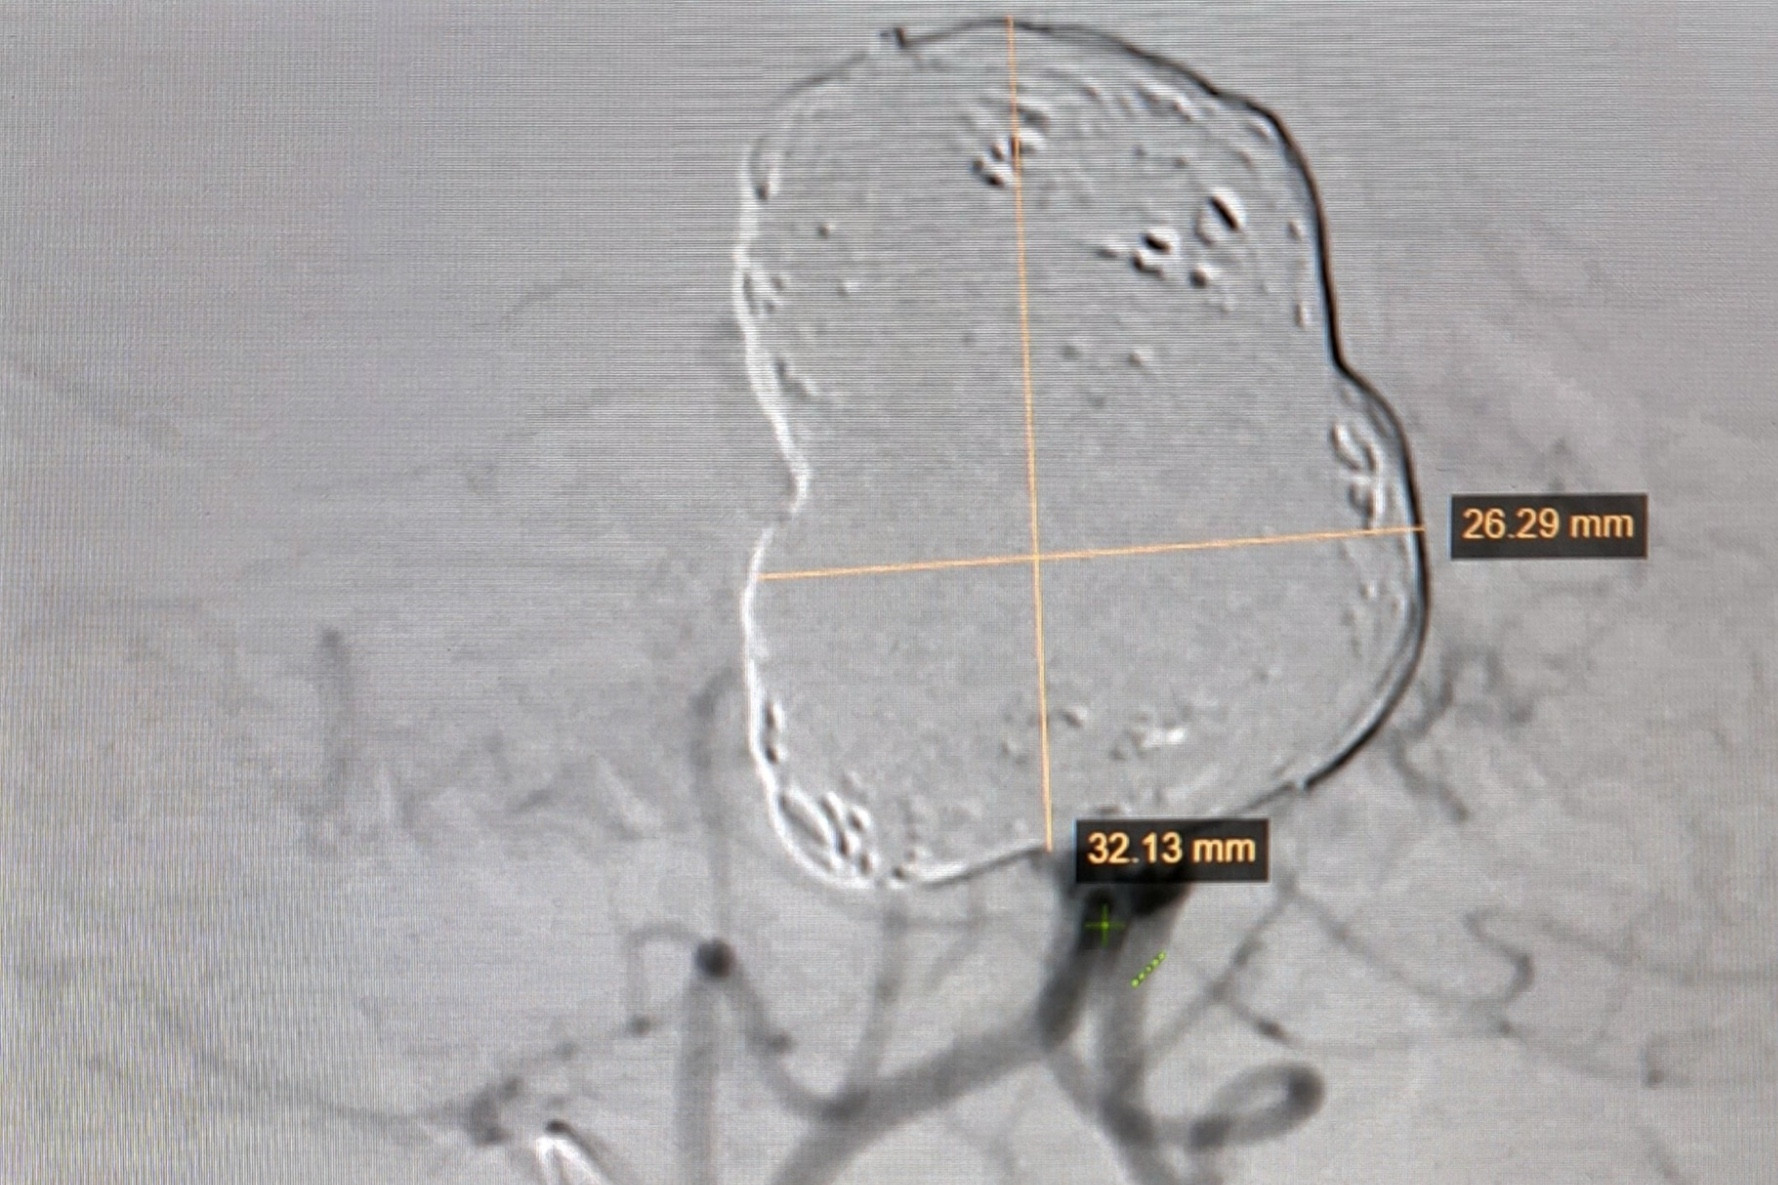

Phát hiện mạch máu não phình to khổng lồ sau cơn sốt